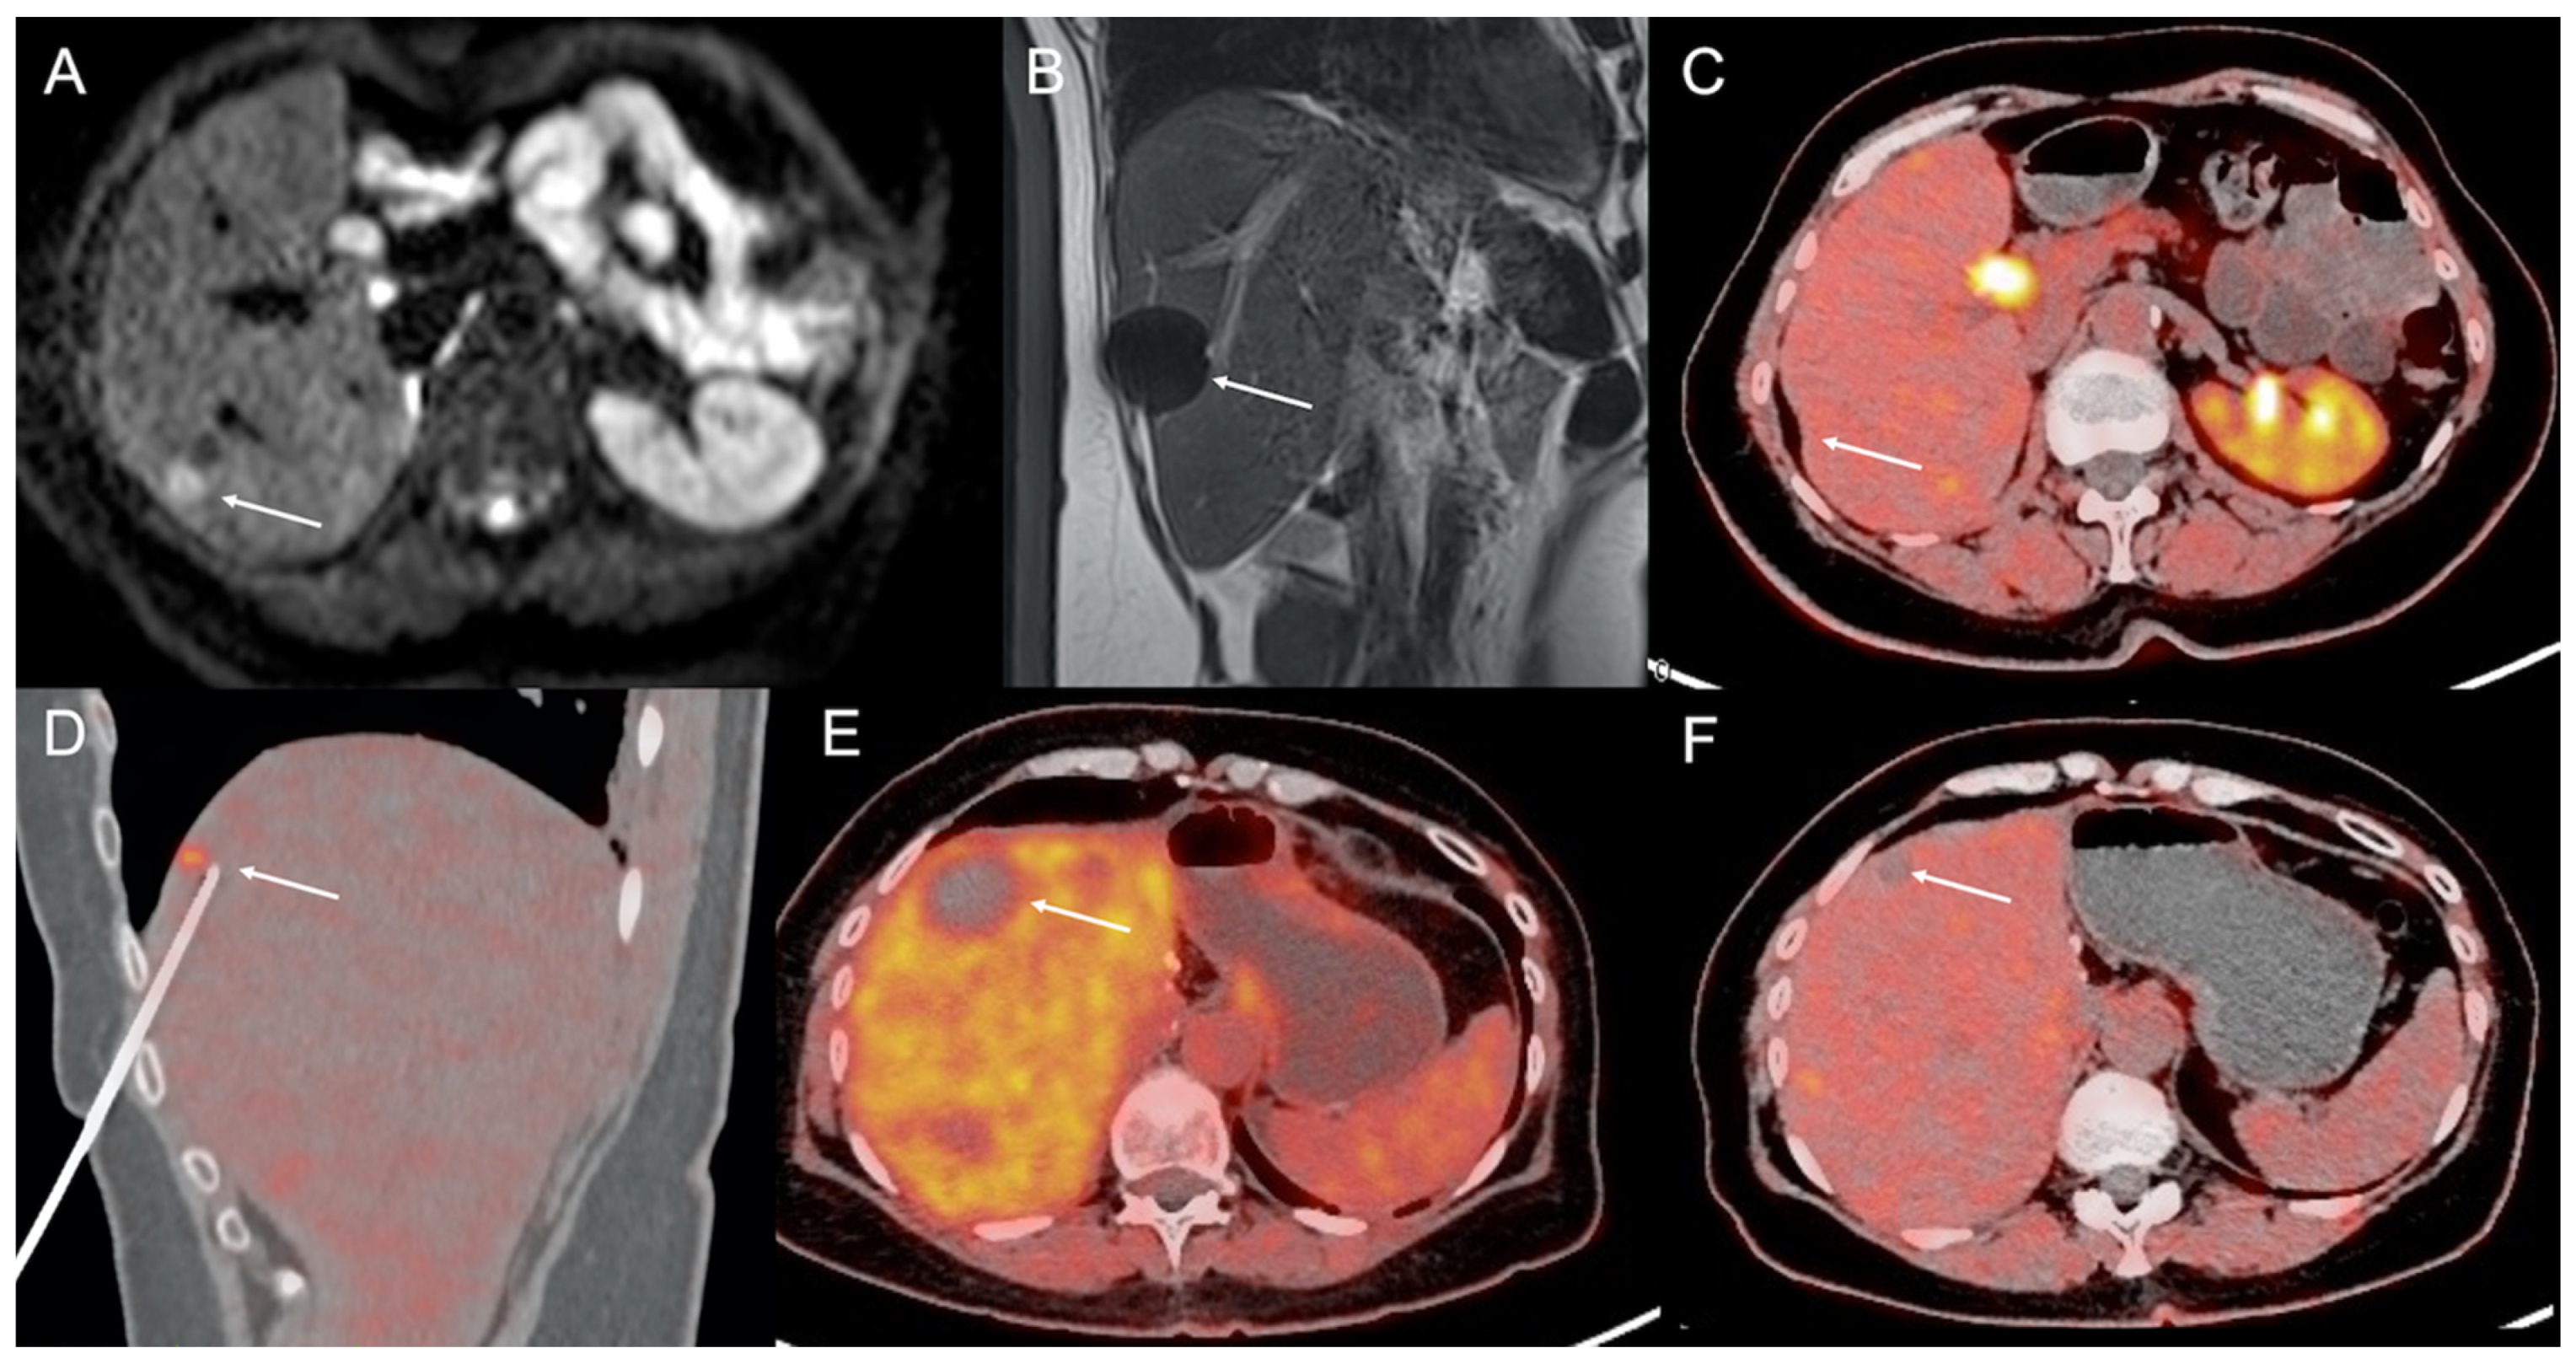

- Imperiale, A.; Garnon, J.; Bachellier, P.; Gangi, A.; Namer, I.J. Simultaneous 18F-FDOPA PET/CT-Guided Biopsy and Radiofrequency Ablation of Recurrent Neuroendocrine Hepatic Metastasis: Further Step Toward a Theranostic Approach. Clin. Nucl. Med. 2015, 40, e334–e335. [Google Scholar] [CrossRef]

- Cazzato, R.L.; Garnon, J.; Ramamurthy, N.; Tsoumakidou, G.; Imperiale, A.; Namer, I.J.; Bachellier, P.; Caudrelier, J.; Rao, P.; Koch, G.; et al. 18F-FDOPA PET/CT-Guided Radiofrequency Ablation of Liver Metastases from Neuroendocrine Tumours: Technical Note on a Preliminary Experience. Cardiovasc. Interv. Radiol. 2016, 39, 1315–1321. [Google Scholar] [CrossRef] [PubMed]

- Cazzato, R.L.; Garnon, J.; Shaygi, B.; Koch, G.; Tsoumakidou, G.; Caudrelier, J.; Addeo, P.; Bachellier, P.; Namer, I.J.; Gangi, A. PET/CT-guided interventions: Indications, advantages, disadvantages and the state of the art. Minim. Invasive Ther. Allied Technol. 2017, 27, 27–32. [Google Scholar] [CrossRef] [PubMed]